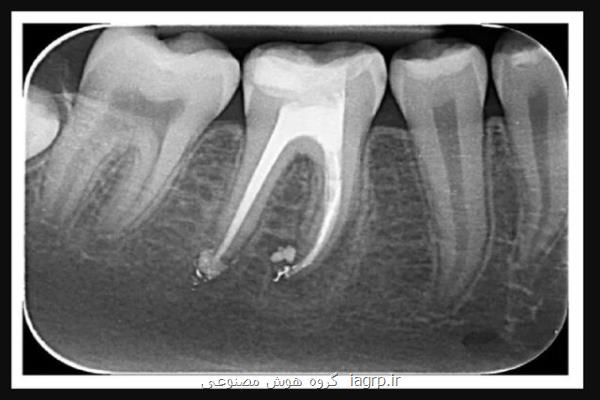

نانو ربات هایی که ریشه دندان را درمان می کنند به گزارش گروه هوش مصنوعی پژوهشگران ˮمؤسسه علوم هندˮ در بررسی جدیدی، از نانوربات ها برای درمان کانال ریشه دندان بهره برده اند. به گزارش گروه هوش مصنوعی به نقل از ایسنا و به نقل از ادونسد ساینس نیوز، افرادی که کانال ریشه دندان را پر کرده اند، می دانند که این روش در بین راحت ترین و آرامش بخش ترین روش های مورد استفاده در دندانپزشکی، رتبه بالایی ندارد اما برای میلیونها بیمار در سراسر جهان، یکی از بزرگترین مشکلات درمان های ریشه، خارج از جراحی دندان رخ می دهد چونکه میزان شکست آنها بعد از درمان، نسبتا بالا است.از آنجایی که دندان بعد از درمان ریشه تا حدودی ضعیف تر از پیش است، علاوه بر شکستگی احتمالی تاج، یک مشکل اصلی که بعد از درمان ریشه رخ می دهد، عفونت باکتریایی است که به پوسیدگی دندان و بروز شکست در پر شدن کانال ریشه منجر می شود. تصور کنید آن دندانی که به غم و اندوه شدید منجر گردیده است، حالا و درست زمانی که تصور می شد همه مشکلات آخر یافته اند، باید بیرون بیاید. چنین عفونت هایی می توانند از باکتری های باقیمانده در اعماق لوله های ریز در عاج دندان ایجاد شوند که به علت پیچیده بودن و هندسه باریک این لوله ها، ضدعفونی کردن آنها حتی با روش های مرسوم، دشوار می باشد اما به لطف تلاشهای گروهی از پژوهشگران "مؤسسه علوم هند"(IISc)، این شکست های بعد از درمان را میتوان با ربات هایی در اندازه نانو که با نیروی مغناطیسی کنترل می شوند، کم کرد.کاربرد نانوفناوری در مراقبت های دندانپزشکیمیکروربات ها و نانوربات ها، یک فناوری درحال پیشرفت هستند که برای مدیریت زباله و همچنین، برای کاربردهای حوزه مراقبت های بهداشتی مورد بررسی قرار گرفته اند. استفاده از آنها بعنوان عوامل ضد باکتری هم شناخته شده است و می توانند از دفاع ایمنی بدن ما فرار کنند. با این حال، پژوهش های کمی به کاربرد چنین نانوربات هایی در دندانپزشکی پرداخته اند."امباریش گوش"(Ambarish Ghosh) و گروهش، نانوربات هایی را توسعه دادند که به اندازه کافی کوچک هستند تا در لوله های عاج دندان قرار بگیرند و به باکتری ها برسند تا آنها را از بین ببرند. این نانوربات ها را میتوان طی درمان ریشه به کار برد و آنها را به صورت خارجی کنترل کرد. همچنین، نانوربات ها می توانند هنگام ضدعفونی کردن دندان صدمه دیده، امکان کنترل دقیق را برای دندانپزشک فراهم نمایند."دبایان داسگوپتا"(Debayan Dasgupta)، از پژوهشگران این پروژه اظهار داشت: پژوهش ما، استفاده از نانوربات های کنترل شده از راه دور را شامل می شود که میتوان آنها را با استفاده از میدان های مغناطیسی کم شدت و بی ضرر هدایت کرد."شانموخ پدی"(Shanmukh Peddi)، از پژوهشگران این پروژه اظهار داشت: این امر ثابت می کند که این روش بسیار بهتر از روش های ضدعفونی کنونی است که برای افزایش عمق نفوذ داروها اجرا می شوند. از آنجائیکه انرژی به سرعت تجزیه می شود، این روش ها در نفوذ دارو به سطوح عمیق تر بافت، ناکارآمد هستند. بنابراین، روش های کنونی نمی توانند سکونتگاه های باکتریایی عمیق را که برای مدت طولانی باقی می مانند و عوارض بعد از درمان را به همراه دارند، درمان کنند.در این پژوهش، از دندان های تازه کشیده شده استفاده شد که آنرا به جای کارآزمایی بالینی، به یک بررسی آزمایشگاهی تبدیل کردند.همچنین، پدی بر اهمیت هدف قرار دادن باکتری "انتروکوک فکالیس"(Enterococcus faecalis) تصریح کرد چونکه این باکتری، شایع ترین علت عفونت بعد از درمان است و به علت توانایی آن در مقاوم شدن به آنتی بیوتیک، یکی از باکتری های در اولویت "سازمان جهانی بهداشت"(WHO) به حساب می آید. پدی اضافه کرد: ما از گرمای موضعی برای از بین بردن این باکتری ها استفاده می نماییم و در نتیجه، احتیاج به آنتی بیوتیک را از بین می بریم.علاوه بر این، نانوربات ها بعد از استفاده، قابل بازیابی هستند و آنها را میتوان به آسانی کنترل کرد تا از لوله های عاج دندان بیرون بروند. به قول داسگوپتا، این خصوصیت بی سابقه است.با از بین رفتن همه باکتری های موجود در لوله های عاج، دندانپزشکان می توانند با آگاهی از اینکه خطر شکست در کانال ریشه بعد از درمان به حداقل می رسد، ایمنی را حفظ کنند. گام بعدی، دور شدن از بررسی های آزمایشگاهی است؛ کاری که پژوهشگران امیدوارند بزودی پس از طریق اندازی یک شرکت نوپا انجام دهند.پدی اظهار داشت: چالش بعدی ما شامل سازماندهی آزمایش های تصادفی سازی شده و کنترل شده روی حیوانات و اثبات اثربخشی آنها در سیستم های زنده است که راه را برای انتقال به آزمایش های بالینی هموار می کند. این استارتاپ هم اکنون درحال بررسی سایر حوزه های پزشکی است که در آنها میتوان از این تکنولوژی بهره برد.گوش امیدوار است که کار گروهش، آغاز یک روش عمومی برای نانوجراحی باشد؛ نه فقط در زمینه دندان. وی ادامه داد: ما نشان می دهیم که نانوربات ها را میتوان در اندام های انسان به کار برد و با باکتری های کشنده مبارزه کرد.این پژوهش، در مجله "Advanced Healthcare Materials" به چاپ رسید. منبع: iagrp.ir 1401/02/25 10:21:11 5.0 / 5 1327 تگها: آزمایش , استارتاپ , بازی , پژوهش مطلب را می پسندید؟ (1) (0) تازه ترین مطالب مرتبط محققان با کمک Claude Mythos مدعی نفوذ به macOS شدند نسخه کامل سکوی ملی هوش مصنوعی تا پایان اردیبهشت در دسترس قرار می گیرد راه اندازی نهاد جدید OpenAI با بودجه ۴ میلیارد دلاری برای استقرار هوش مصنوعی در سازمان ها آیا زمین برای هوش مصنوعی کوچک شده است؟ نظرات بینندگان در مورد این مطلب لطفا شما هم در مورد این مطلب نظر دهید = ۸ بعلاوه ۳ نظر دادن